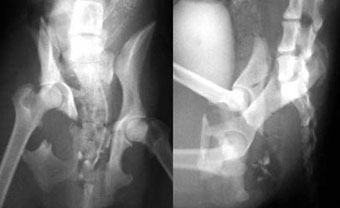

他院からの依頼症例

体重3kg、5歳齢の猫。

腸骨体と恥骨骨折および仙腸関節離断をおこしていました。

写真上段: 手術前

写真中段: 手術後

6本の創外固定ピンを刺入して骨盤構造を支えています。

写真下段: ピン抜去後

骨盤構造は正常に近い状態に回復しています。 |